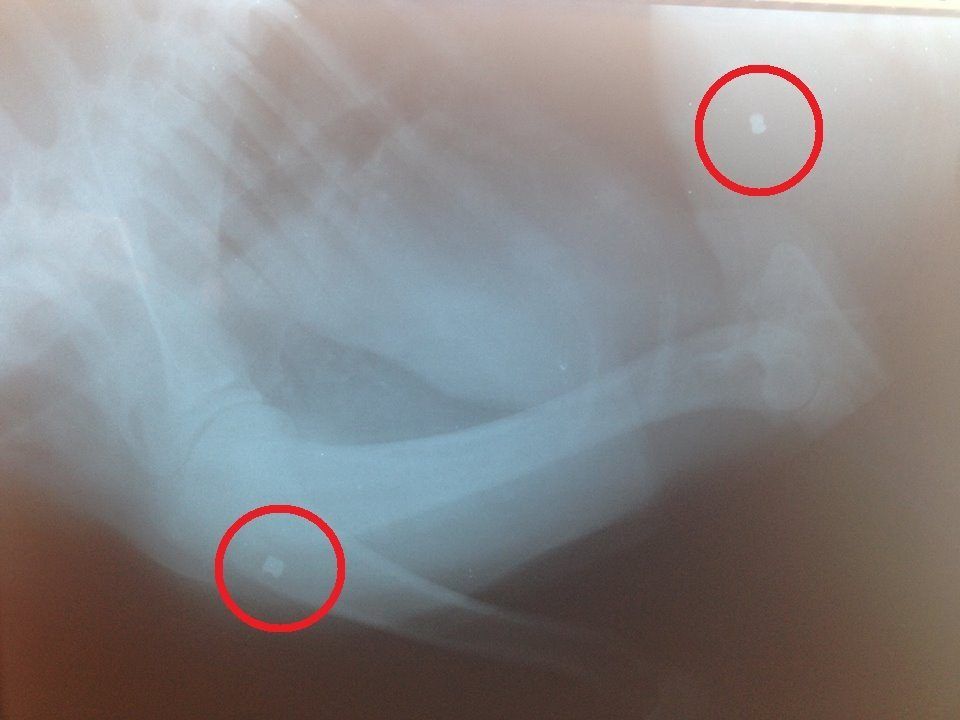

IrmaMoulkiKorinthias%20%282%29Η ακτινογραφία δείχνει τα δύο σφαιρίδια του αεροβόλου που εντοπίστηκαν στο σώμα της Ίρμας.